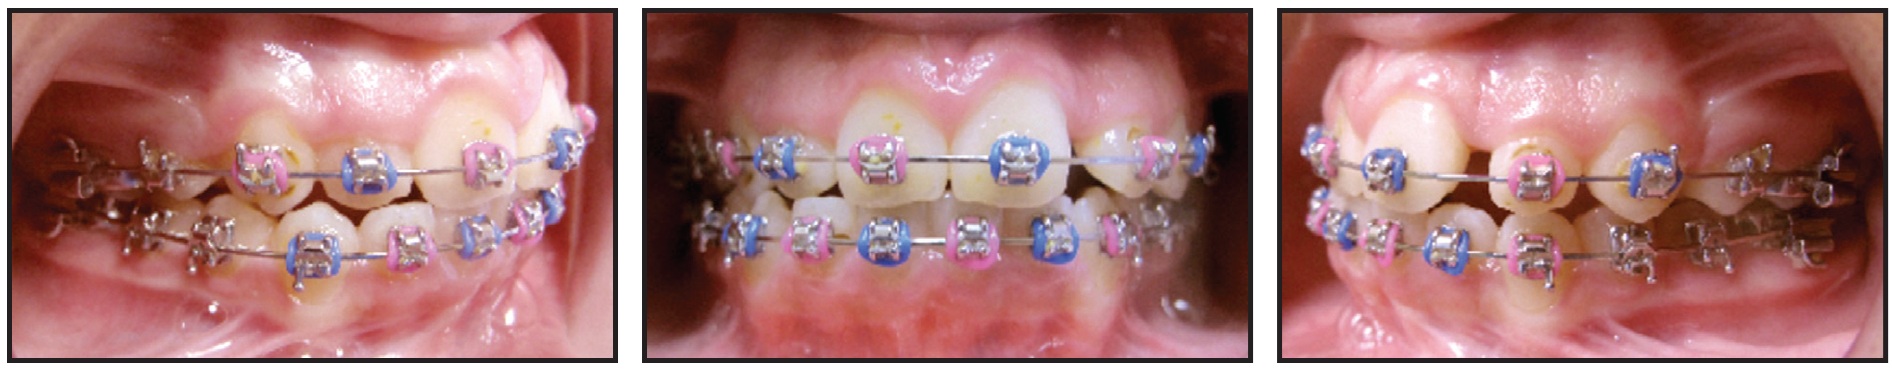

This 10-year-old female presented with upper crowding and protrusive lower incisors (Fig. 13). The upper first premolars were extracted to relieve the crowding, but no extractions were performed in the lower arch.

Fig. 13 10-year-old female patient with upper crowding and protrusive lower incisors before treatment.

As a result, the lower incisors were further proclined, and we ran out of overjet trying to close the upper spaces (Fig. 14).

Fig. 14 After upper first-premolar extractions and 15 months of treatment, lower incisors further proclined, with insufficient overjet for upper space closure.

We had to extract the lower left first premolar to shift the lower midline and upright the lower incisors enough to permit the upper space closure.

The lesson here is to keep the lower incisors upright. In an asymmetrical Class II case, that might call for a three-premolar extraction pattern. In this particular patient, it also helped with the alignment and allowed complete eruption of the lower left second molar (Fig. 15).

Fig. 15 Patient after 25 months of treatment, following extraction of lower left first premolar to allow uprighting of lower incisors.